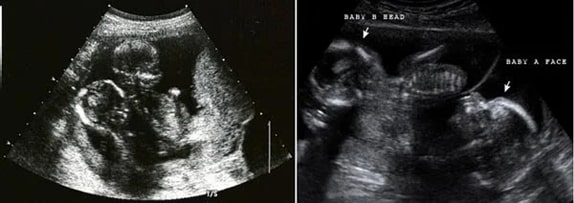

Ayrıca ikiz gebelik ultrason görüntüleri de listemizde bulunmaktadır. Ek olarak, gebelikte bebeğin boyu ve kilosu da kişiden kişiye değişiklik gösterse bile bilgi edinmek için eklenmiştir. Ultrason görüntüleri yazılarından önce isterseniz aşağıdan hamilelikte hafta hafta karın büyümesi galerimize göz atabilirsiniz.

15 Haftalık İkiz Gebelik Ultrason Görüntüleri

16 Haftalık İkiz Gebelik Ultrason Görüntüleri

17 Haftalık İkiz Gebelik Ultrason Görüntüleri

18 Haftalık İkiz Gebelik Ultrason Görüntüleri

19 Haftalık İkiz Gebelik Ultrason Görüntüleri

20 Haftalık İkiz Gebelik Ultrason Görüntüleri